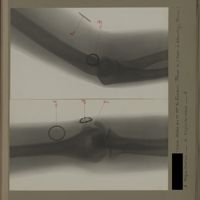

0134 - Page 22 - [Radiographies du coude et du tiers supérieur de l'avant-bras]0134 - Page 22 - [Radiographies du coude et du tiers supérieur de l'avant-bras]